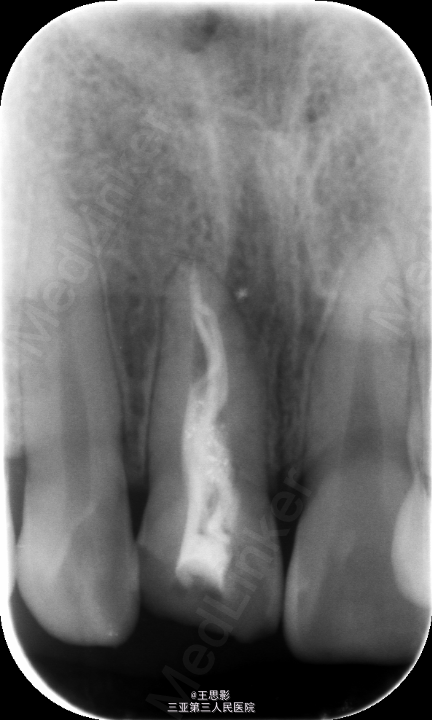

11斜行缺损,无叩痛,无松动,X线示根充欠密实

11牙体缺损,根充不良,处理,去除原充填物,再治疗锉去除牙胶,预备后,试尖,欠长1mm,重新H锉疏通,到达长度后,以大锥度牙胶完成热压充填